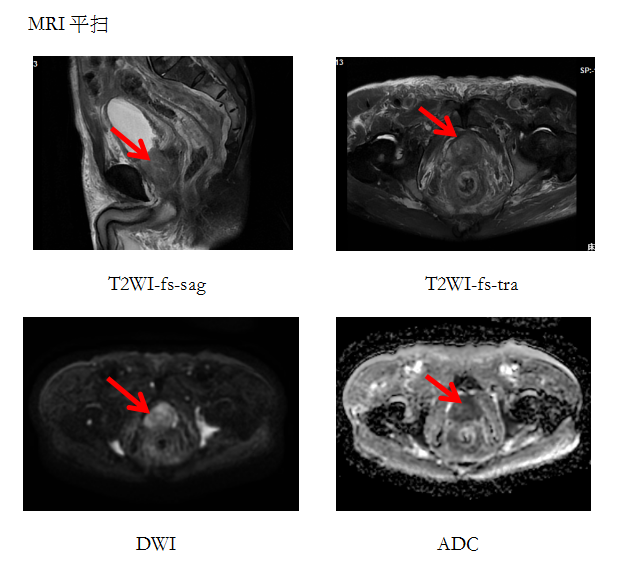

患者何大爷,最近出现尿频、排尿疼痛,肉眼血尿等症状。于是到医院检查,报告上显示“PSA”升高,115.15ng/mL。医生建议做个前列腺增强磁共振。

异常增大的前列腺,增强后呈不均匀明显强化并可见盆腔多发淋巴结转移及骨质破坏。

随着MRI技术的高速发展,前列腺MRI已成为前列腺癌诊断和定位的重要影像技术。MRI因具有无创、无电离辐射、软组织分辨率高、可反映组织器官功能学及生化代谢改变等优势,能够多方位成像,能清晰显示前列腺包膜是否完整,了解肿瘤有无扩展至包膜及精囊腺、直肠、膀胱等周围组织及器官,有无盆腔淋巴结转移及盆骨转移等,并可以定位引导前列腺靶向穿刺活检,使其在诊断和评估前列腺癌时表现出较高的应用价值。所以,患了前列腺疾病的患者应该选择磁共振进行辅助检查,尤其是在PSA升高或直肠指检异常的情况下。